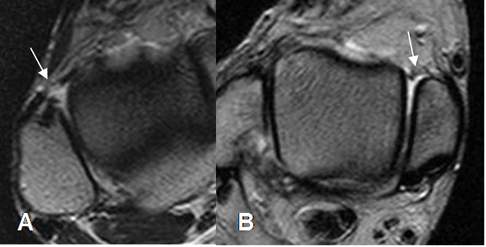

Fig 61. Esguince grado II.

A: RM axial y B: RM coronal en STIR. Fibras hiperintensas del LPAP por distensión, pero se conservan integras.